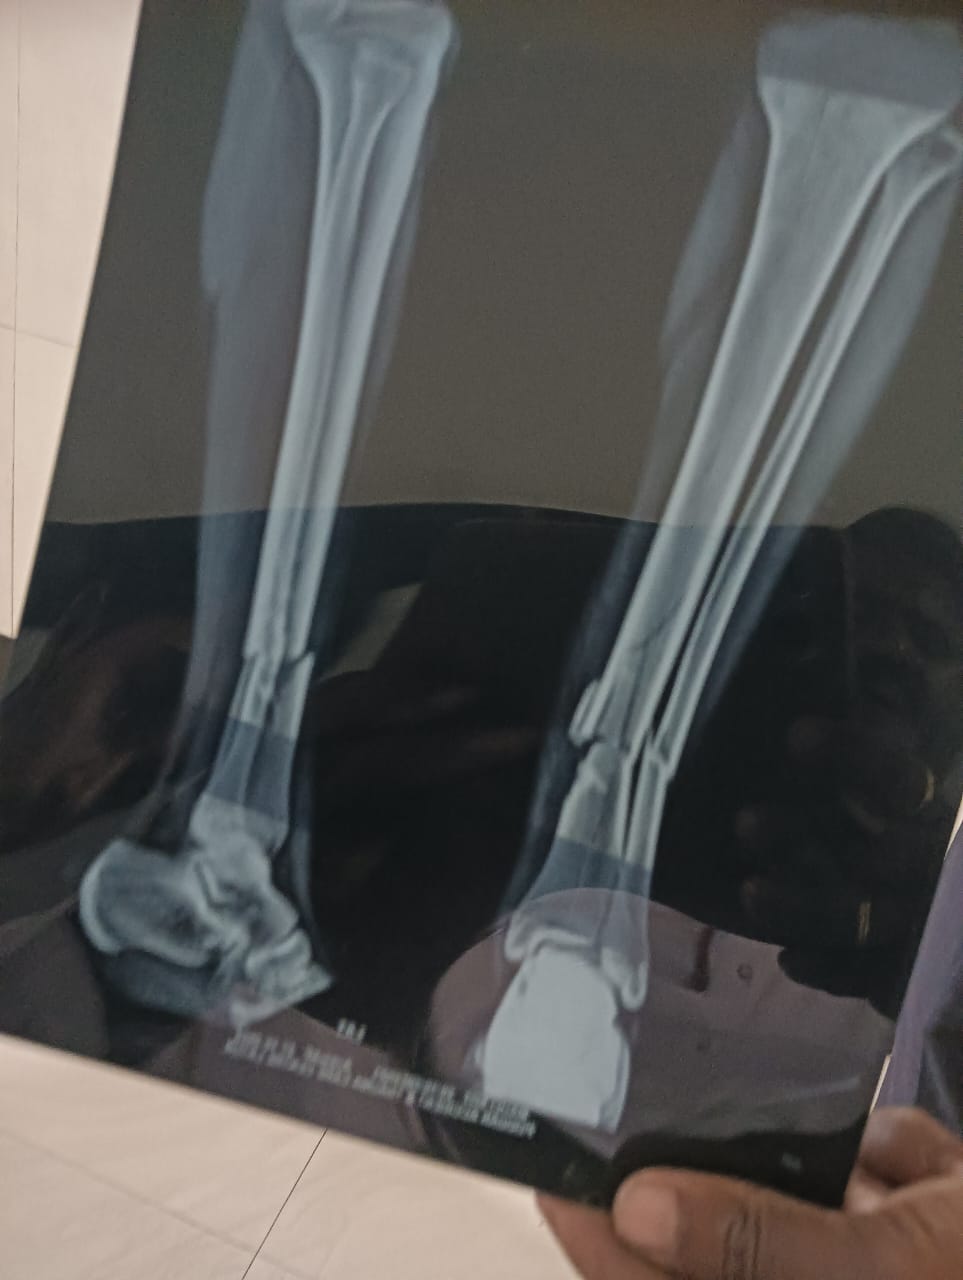

1लातूर टाकळी माऊली सोड अठरा वर्षे तरुणाची निर्गुण मारहाणीत हत्या जातीवादाचा बळी! अभा माळी महासंघाचे राष्ट्रीय अध्यक्ष सत्यशोधक शंकरराव लिंगे प्रदेशाध्यक्ष गौतम क्षीरसागर यांनी पीडित कुटुंबाची सांत्वन पर भेट घेऊन शिवक्रांती टीव्हीसाठी आई-वडिलांची नातेवाईकांची मुलाखत घेतली माऊली उमाकांत सोड या तरुणाची अमानुष मारहाण करून डोक्याच्या खालील सर्व शरीराची हाडे मारून मारून चुरा केलेली होती हत्या करण्यात आली v Do फोटो पहा

या कुटुंबाची अ.भा.माळी महासंघाचे राष्ट्रीय अध्यक्ष, सत्यशोधक शंकरराव लिंगे, प्रदेशाध्यक्ष गौतम क्षीरसागर यांनी पीडित कुटुंबाची सांत्वन पर भेट घेऊन शिवक्रांती टीव्हीसाठी आई-वडिलांची नातेवाईकांची मुलाखत घेतली माऊली उमाकांत सोट या तरुणाची अमानुष मारहाण करून डोक्याच्या खालील सर्व शरीराची हाडे मारून मारून चुरा केलेली होती. अशाप्रकारे हत्या करण्यात आली. यांचे वडील उमेश यशवंत सोट, आई अर्चना उमाकांत सोट, भाऊ अभिषेक उमाकांत सोट अनिल शंकरराव सोट, श्याम खांडेकर, भाऊसाहेब पाटील दगडू बने, अनिल भोईकर, भाऊसाहेब सोट इत्यादी उपस्थित होते. सत्यशोधक शंकरराव लिंगे अखिल भारतीय माळी महासंघ, राष्ट्रीय अध्यक्ष, गौतम शिरसागर, अखिल भारतीय माळी महासंघ प्रदेशाध्यक्ष यांनी समक्ष टाकळी जिल्हा लातूर येथे त्यांच्या घरी जाऊन समक्ष घेतलेली मुलाखत यावेळी मयत तरुणाचे वडील आई नातेवाईक इत्यादी उपस्थित होते एफआयआर मधील मजकूरानुसार बातमी देत आहोत.

सर्व रा. टाकळी ता. जि. लातूर हे सर्वजण माझ्या जवळ आले व त्यांनी तु आमच्या पोरीला पळवुन नेले. काही करुन लाथाबुक्क्यांनी मारहाण करण्यास सरुवात केली. मला ओढून, गोपाळ डुरे, कमलाकर डुरे यांनी काठीने व गोविंद डुरे, मनोज उफाडे यांनी शॉकऑब्झाॅर्व्हर्सने जिवे मारण्याचे उद्देशाने मारहाण करीत होते. मी जोरजोराने ओरडत होतो. त्यावेळी गावातील बरेच लोक तेथे सोडण्यासाठी कोणीही समोर येत नव्हते. मला मारहाण करीत असतानां त्यांनी माझ्या दोन्ही पायाचे मध्यावर मारुन चार तुकडे केले व दोन्ही हातावर डोक्यात, पाठीवर व इतर ठिकाणी काठीने व रॉडने मारहाण करत होते, तेव्हा कमलाकर डुरे यांनी “याला मारून टाका हा जिवंत नाही राहीला पाहीजे” असे म्हणून मारहाण करीत होते. मारल्यानंतर वरील सर्वजण “चला हा मेला. आता याच्या घराकडे जाऊ” असे म्हणून हे सर्वजण निघुन गेले असल्याचे सांगीतले. आम्ही मुलगा माऊली यास दिनांक 28/11/2024 रोजी 12.30 वा. सुमारास ऍडमिट करून उपचार सुरु केले. मुलगा माऊली यांस ऍडमिट केल्यानंतर मुलगा माऊली याच्या प्रकृती मध्ये सुधारणा होत नसल्याने तेथील डॉक्टरांनी त्यास 30/10/2024 रोजी उपचारासाठी गैलक्सी हॉस्पीटल लातूर येथे रेफर केले असुन मुलगा अजून सुद्धा बेशुद्ध च होता. 27/10/2024 रोजी रात्री 09.00 वा चे सुमारास माझा लहान मुलगा माऊली उमाकांत सोट वय 18 वर्षे रा. टाकळी यास आमच्या गावातील